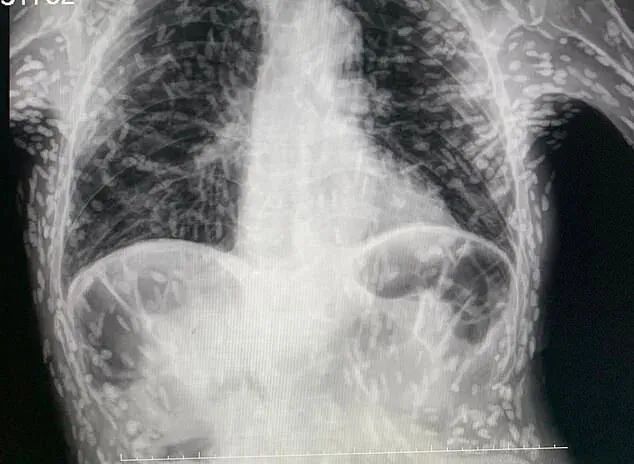

据巴西媒体报道,一名男病患日前因持续咳嗽长达2个多月就医,结果经检查竟发现,他体内各部位已爬满寄生虫,且X光上所照出的数百个白点,全都是寄生虫卵的钙化残壳,而这张恐怖影像在推特上曝光后随即引发热议,让人看得起鸡皮疙瘩。

据这名圣保罗州Botucatu医院任职的男医师Vitor Borin de Souza表示,事后经化验证实患者感染了囊虫病,这是一种由猪肉绦虫幼体所引发的病症。

Vitor 进一步解释,患者之所以会感染此病,最常见的感染途径是吃了不洁食物误食虫卵,而白色点点其实是幼虫已经钙化的包囊,对人体健康并不具威胁,在大部分的情况下,患者无需接受特别治疗,但若寄生虫跑到大脑、髓质、眼睛等部位恐引发致命感染,除了会引发头痛、脑积水、癫痫等症状外,没及时治疗甚至还恐因此丧命,所以为了慎重起见, 事后已安排患者接受头部MRI检查。